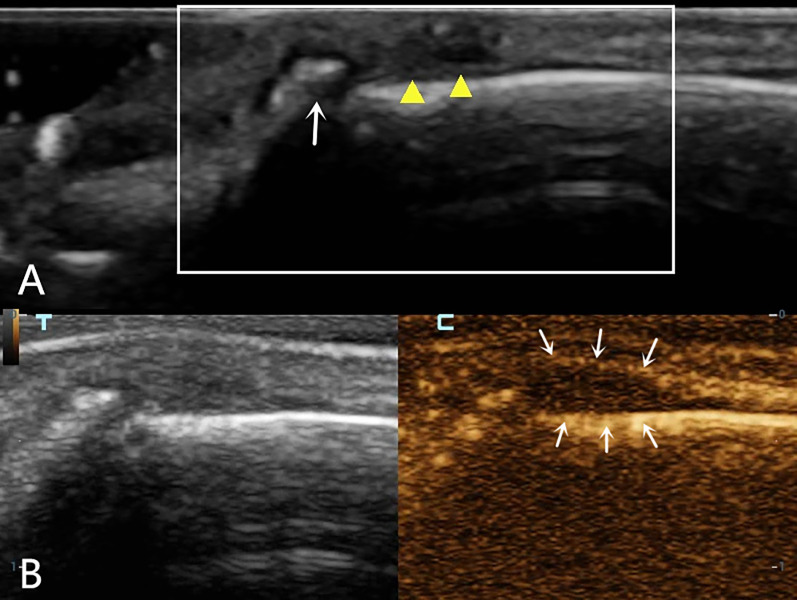

Background: By combining high-frequency and contrast-enhanced ultrasound (CEUS), the position of the severed end of a finger extensor tendon injury and the injury classification can be determined as part of a comprehensive preoperative evaluation in clinical practice. However, there have been no reports of high-frequency ultrasound combined with CEUS for the preoperative diagnosis of human finger extensor tendon injury.

Cases presentation: One case of complete rupture of the extensor tendon was diagnosed by ultrasound, which was completely consistent with the surgery; one case of incomplete rupture was ultimately confirmed clinically; and one case of distal phalangeal bone base avulsion fracture with tendon contusion and missed diagnosis on the first radiographic examination was confirmed by follow-up radiographic examination.

Conclusions: Different types of finger extensor tendon injuries exhibit distinctive contrast-enhanced ultrasonography findings. Combined high-frequency and contrast-enhanced ultrasound can accurately locate the position of the severed end of the finger extensor tendon injury before surgery while observing the contrast agent filling area to clarify injury classification, providing a reliable imaging basis for clinical practice and ultimately developing personalized diagnosis and treatment plans for patients to ensure minimal trauma and pain, as well as optimal treatment effects.